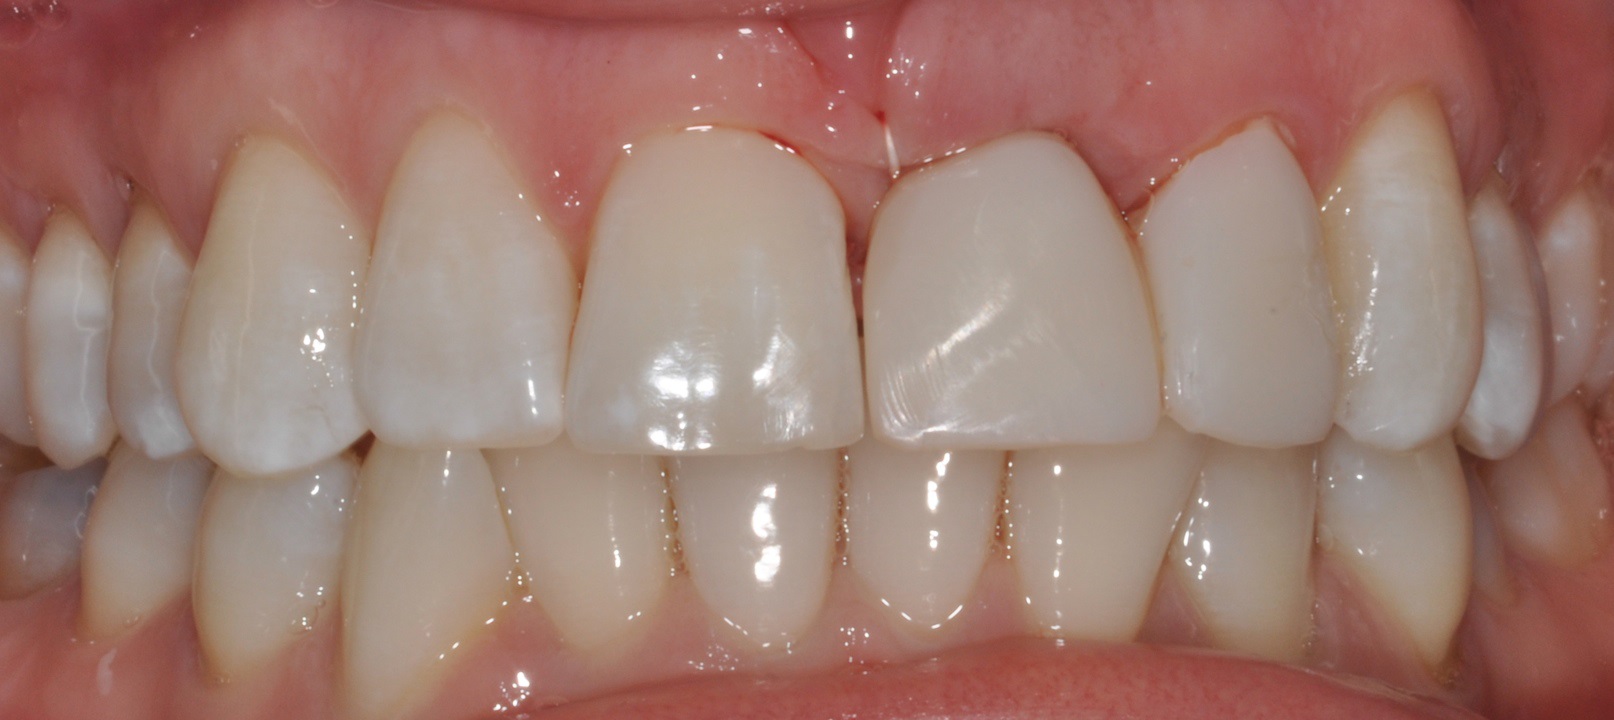

01/16 - Situation before extraction with single tooth crowns on 21 and 22

Socket preservation with cerabone® - Dr. R. A. Nader